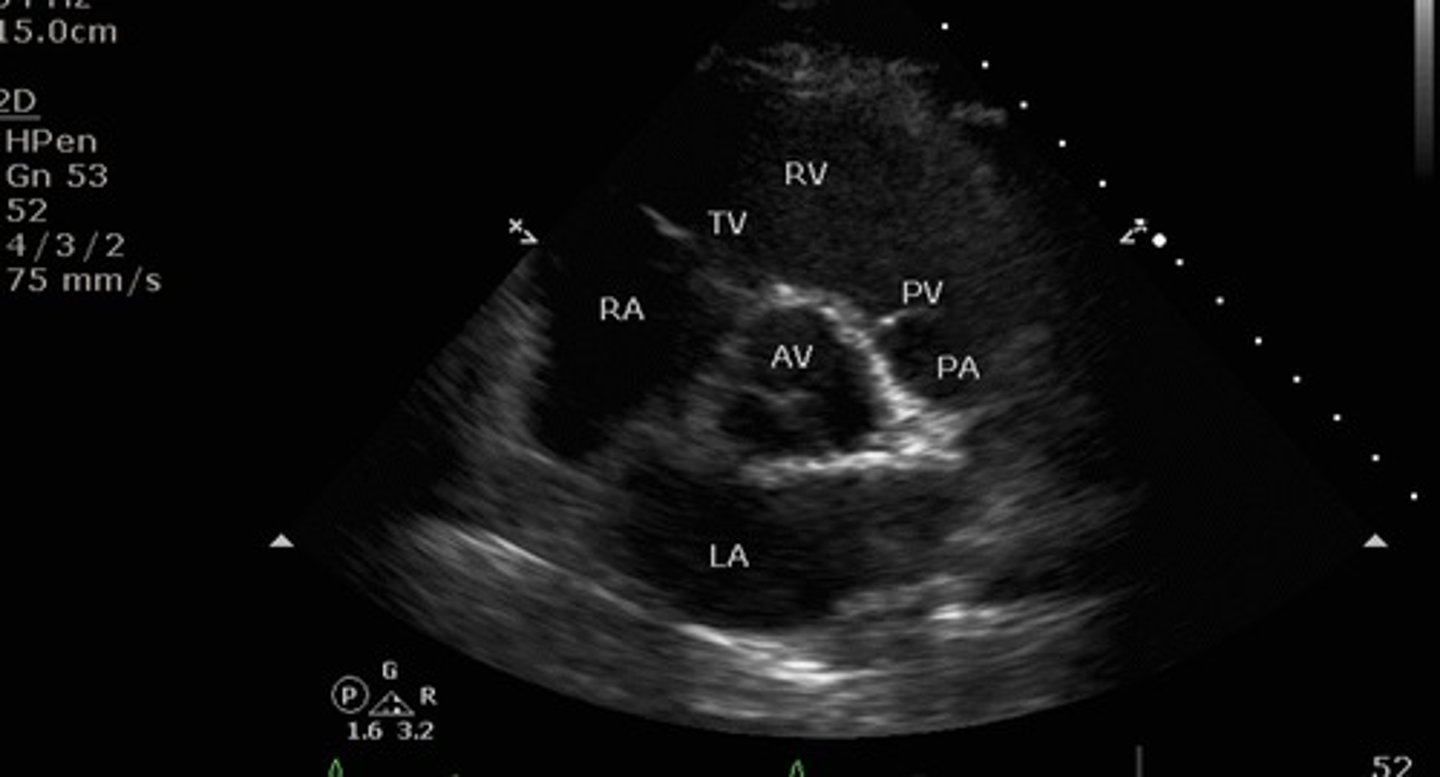

Parasternal short axis aortic valve view

What view is this?

1. right atrium

2.tricuspid valve

3.right ventricle

4. pulmonic valve

5.pulmonary artery

6. left atrium

red circle: aortic valve

identify the numbered and circled structures